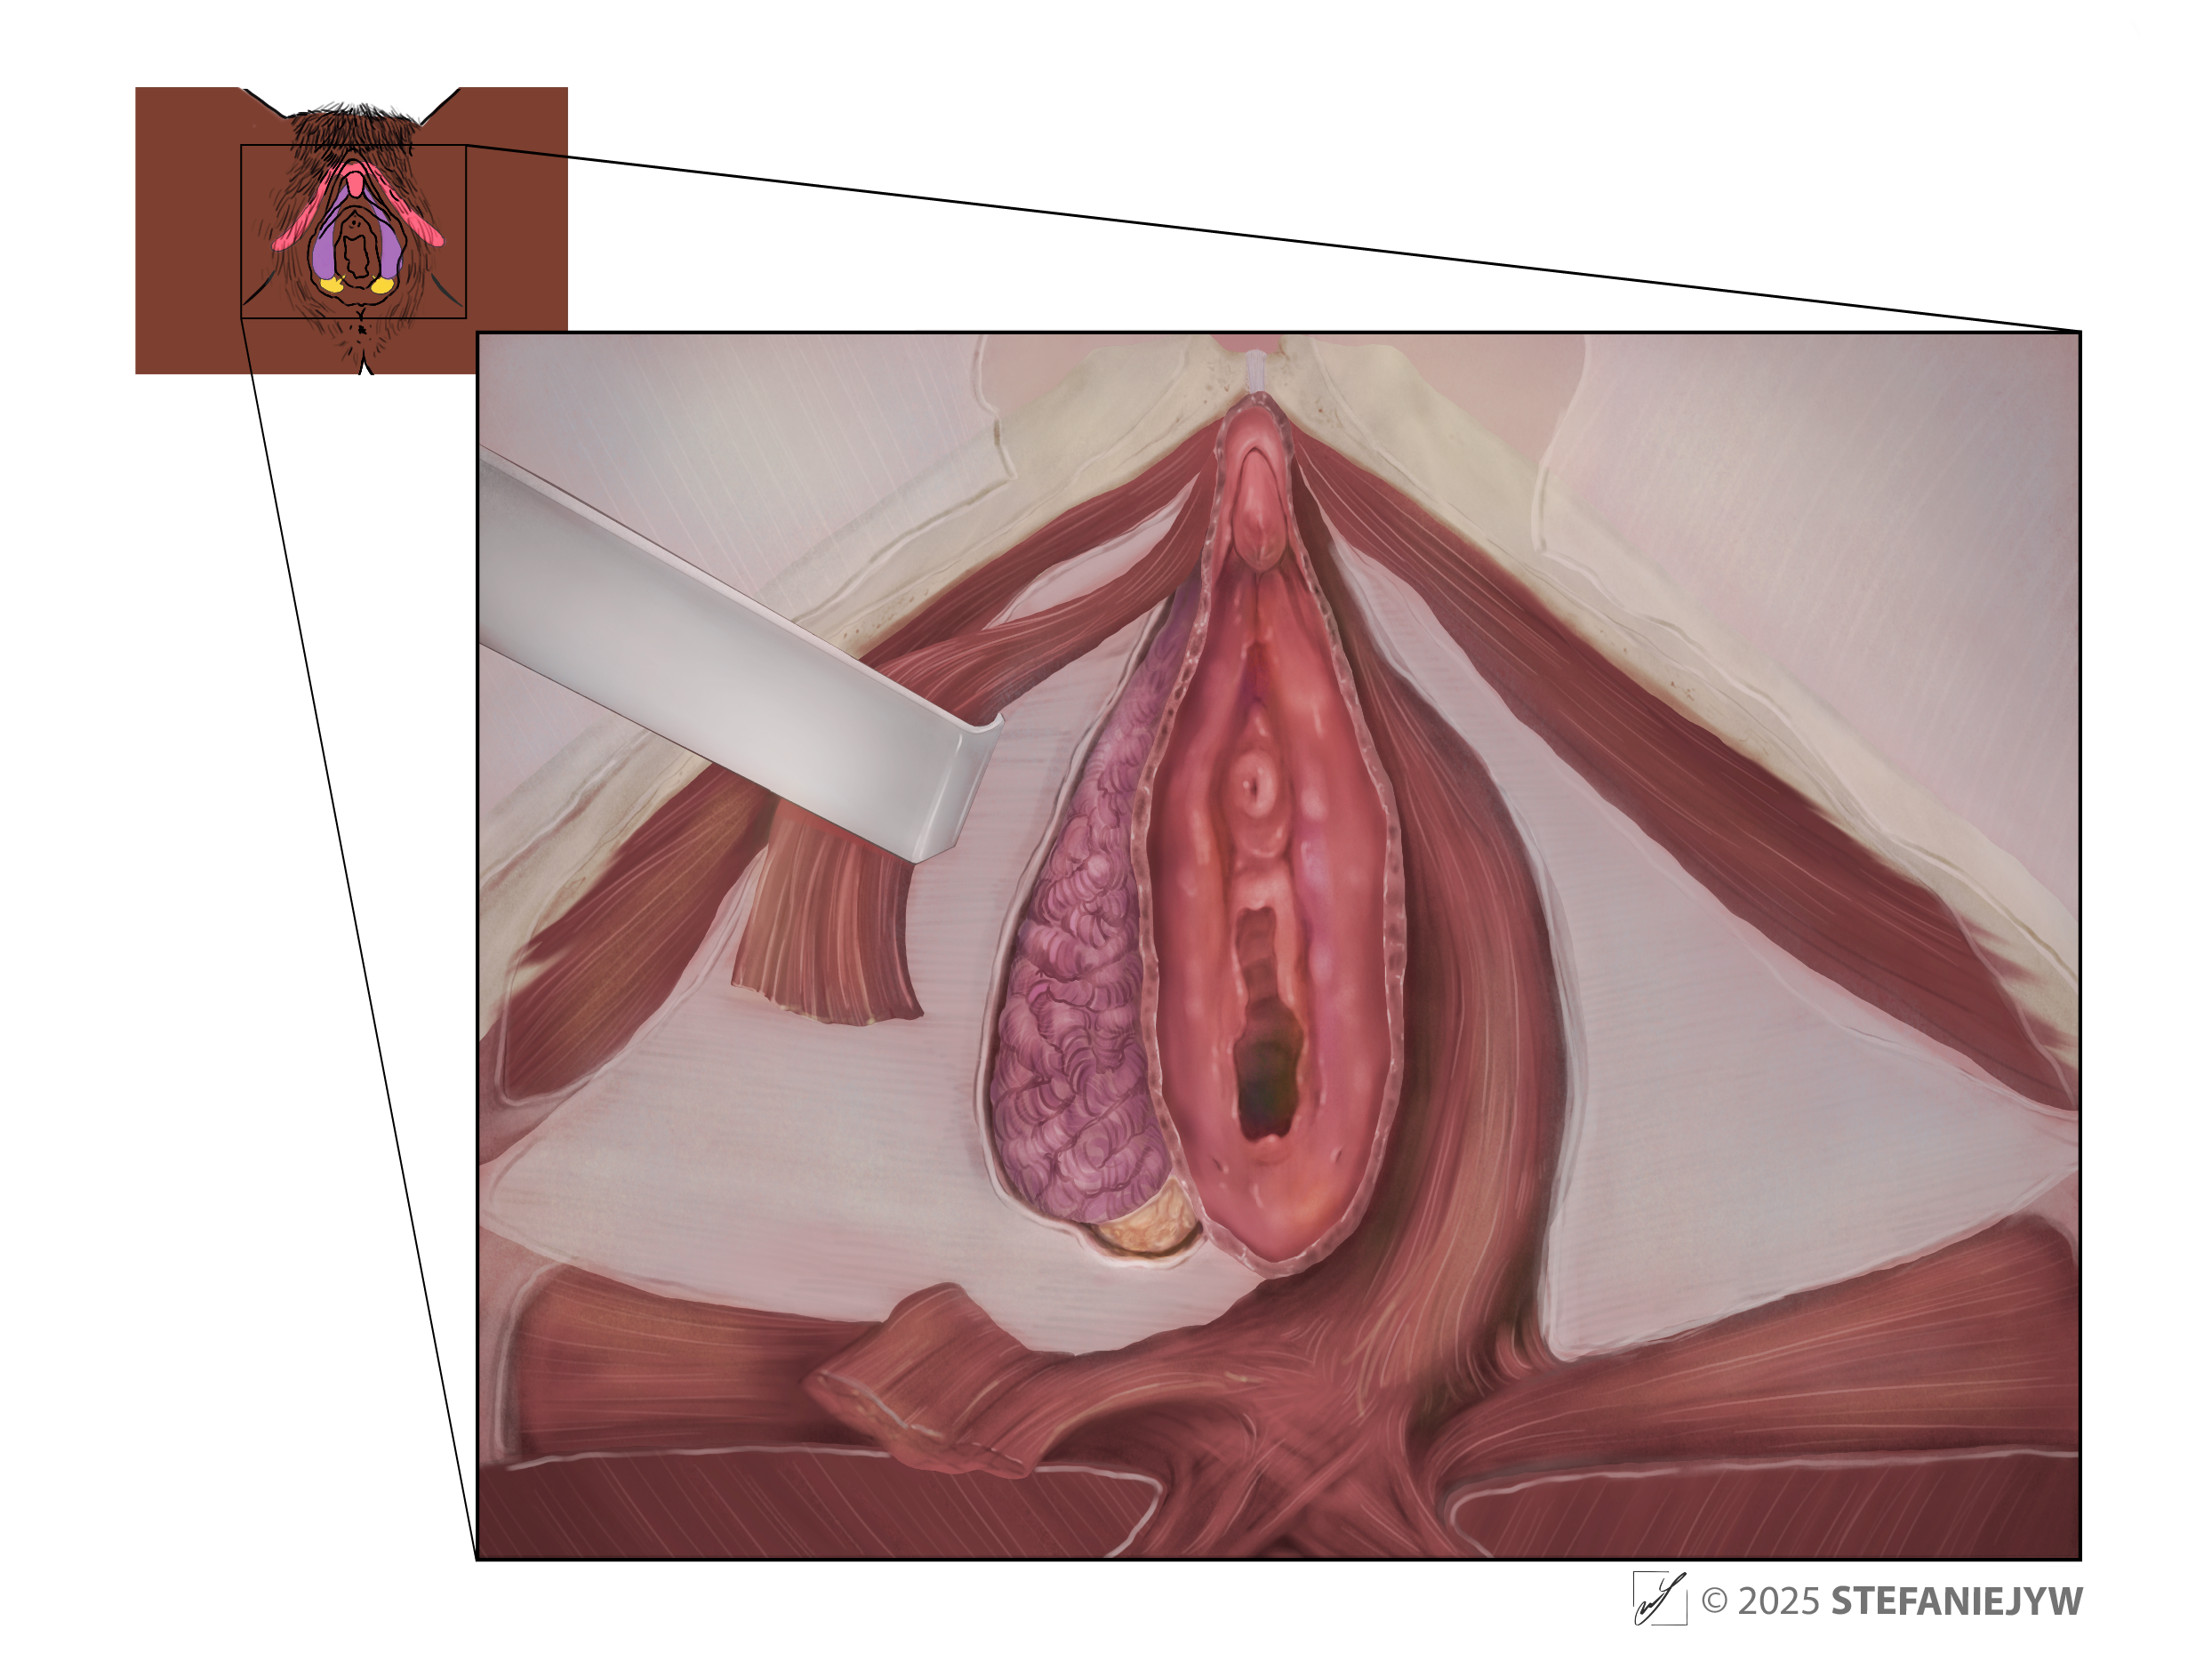

Series: Inclusive Anatomy